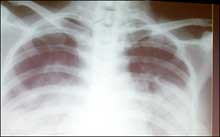

This undated file photo shows a chest X-ray of a SARS victim. Scientists conducting research in eastern China have found that a medicine used to treat schizophrenia is effective in treating patients with the deadly SARS disease. [AFP]